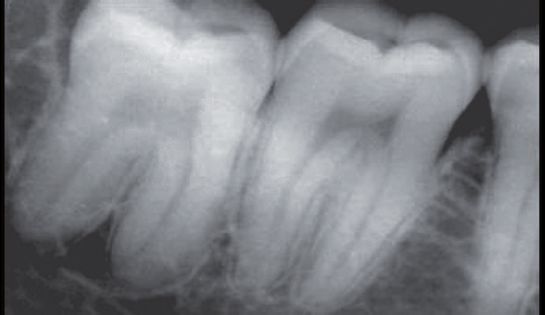

A.水平智齿仅露出远中牙冠

B.X线显示阻生智齿水平中位

C.直接分牙法并未切开、翻瓣、去骨拔除

D.智齿拔除,牙槽窝完好